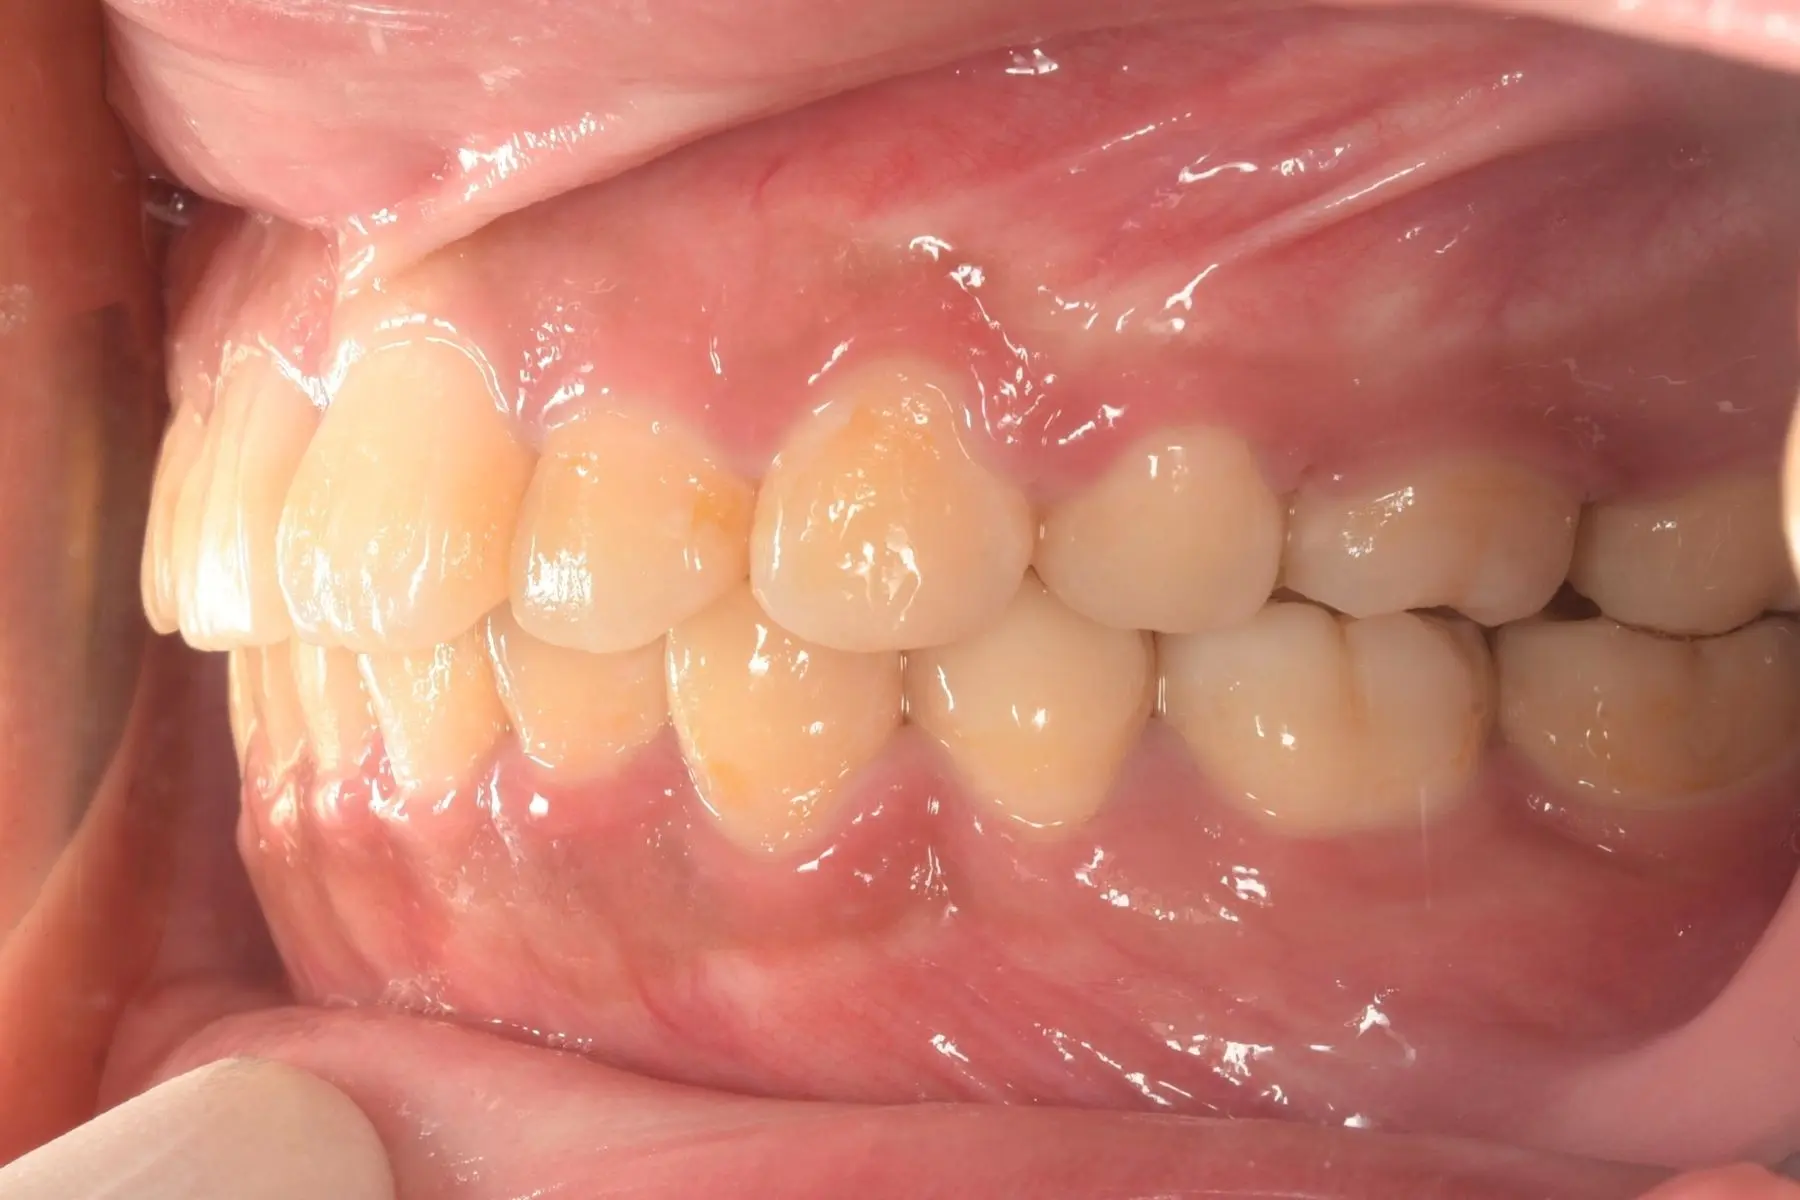

術前術後對比

自鎖式矯正_術前

自鎖式矯正_術後